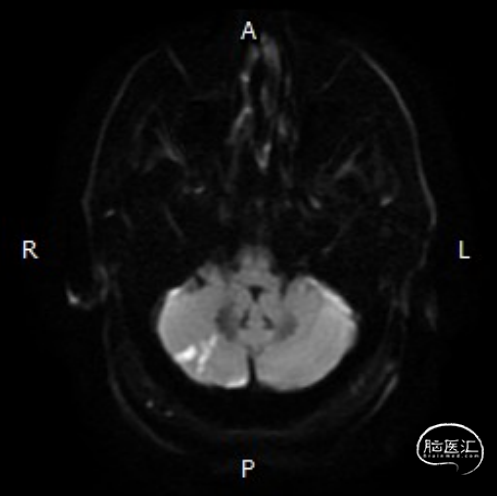

➢头颅MRI:

双侧小脑半球以及桥脑急性缺血性梗死。